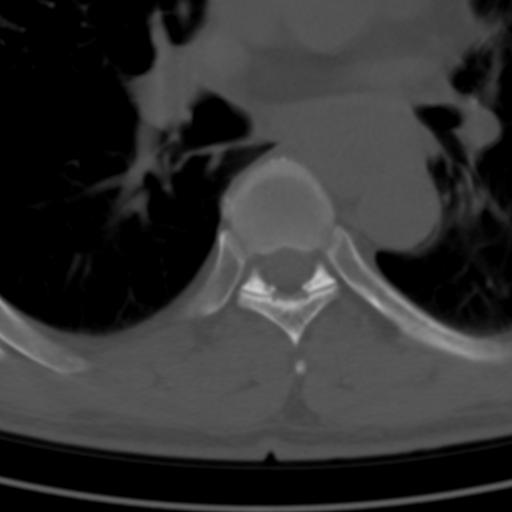

标题: CT25189:胸椎ct,请会诊!

既往食管癌,现行ct检查!

中上段食道癌,椎体轻度退变。

椎体退行性改变,食管癌。